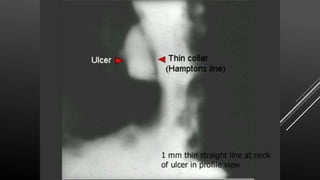

Pathogonomic sign Hamptons line

(a thin sharp lucent line

Carman’s

meniscus ( A